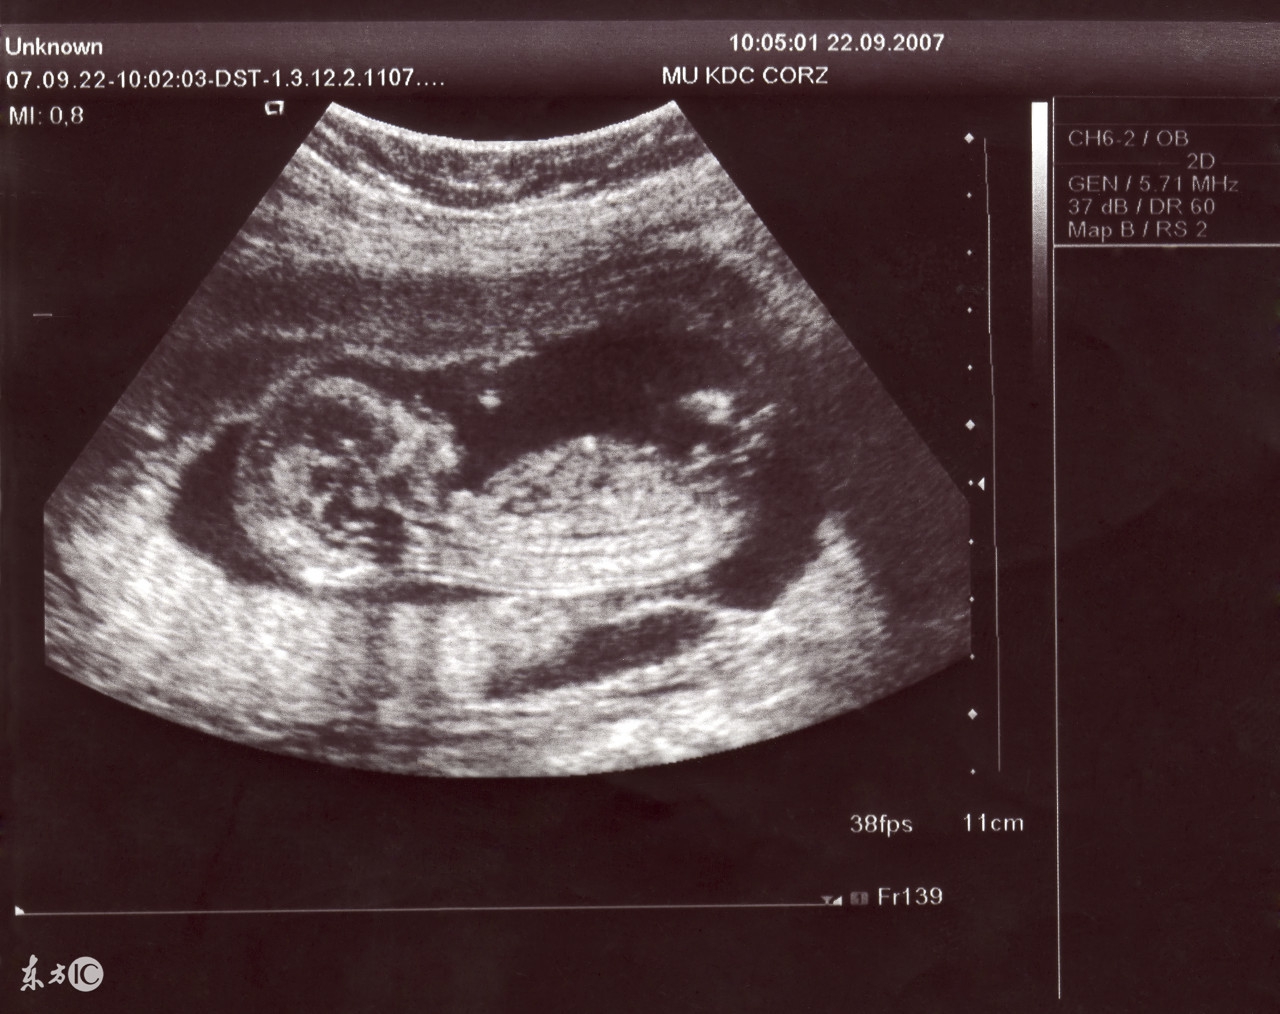

1、普通B超:也有人称为“黑白超声”,医学上称为二维超声、黑白色;

4、二维彩超:黑白色、分辨率比黑白超声高,会用彩色标注心脏、血流等指标;